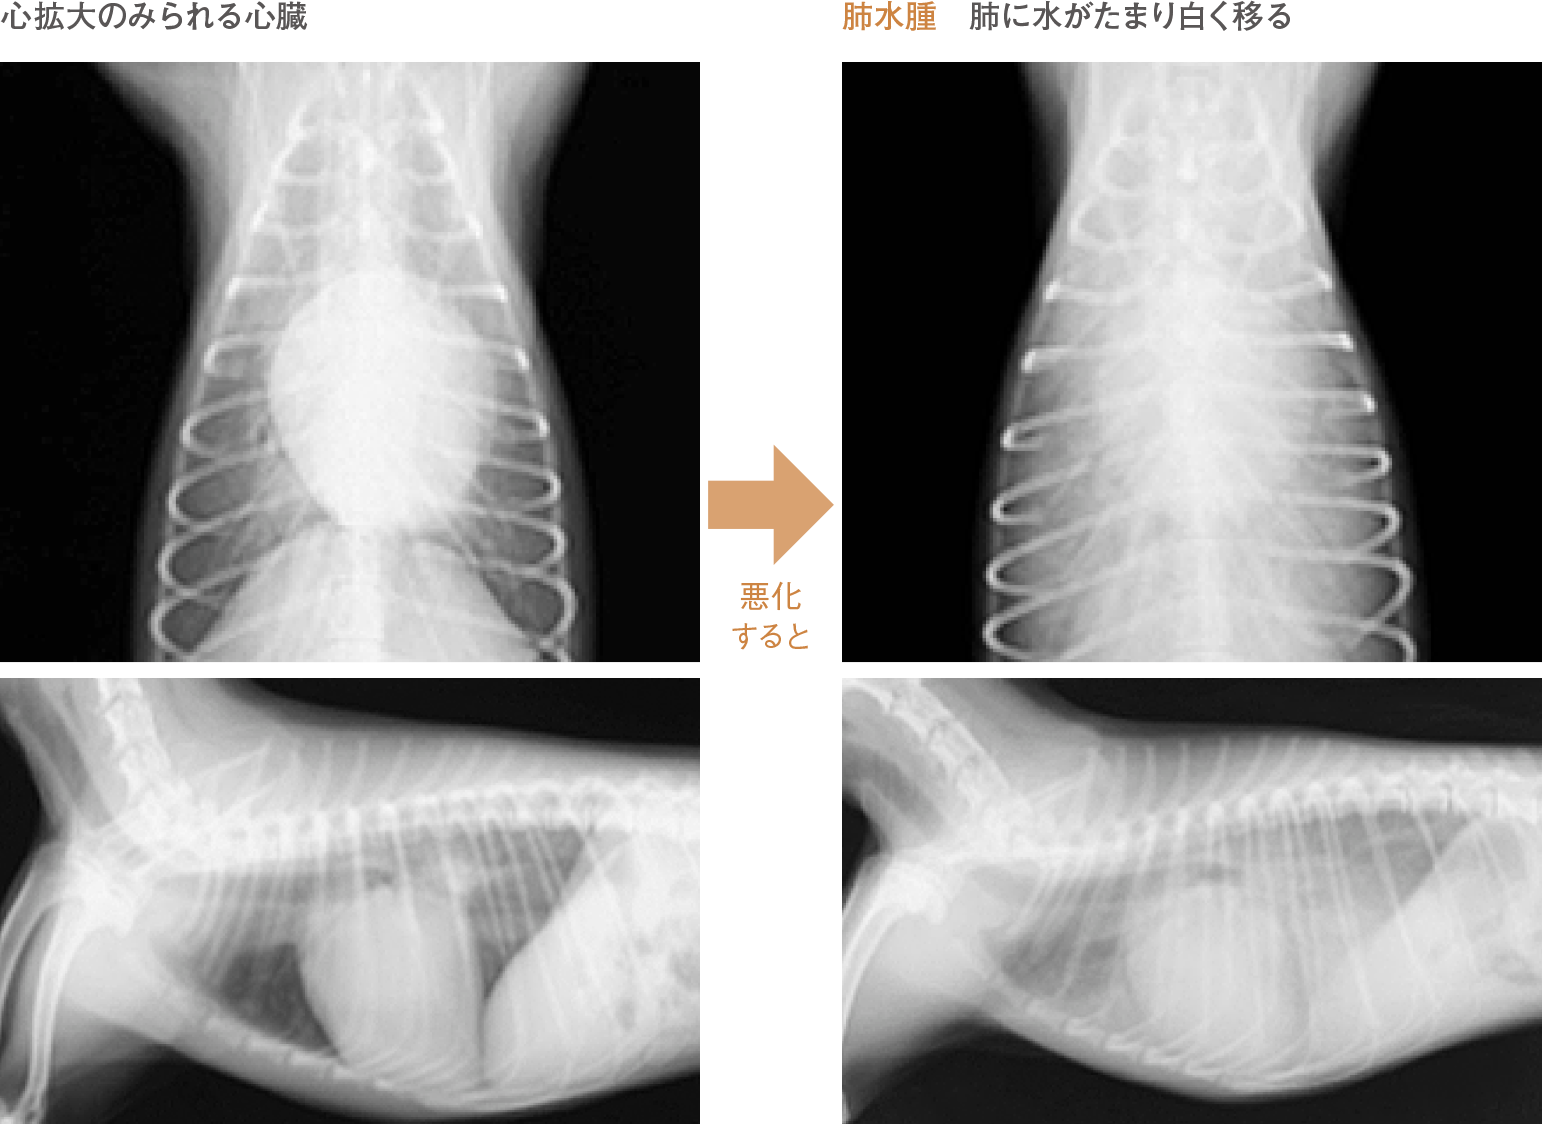

X線検査

負担のかかった心臓は徐々に肥大していきます。また、さらに心機能が悪化すると血液は全身をうまく循環できなくなり、肺に水がたまる(肺水腫)、胸や腹部に水がたまる(胸水、腹水)ことがあります。これらを確認するのにX線検査が有用です。

僧帽弁閉鎖不全症は心臓の血流を調整する僧帽弁という弁の機能が低下し、 本来一方通行である血液の流れに逆流がおきる病気です。中年齢以降の犬に多くみられます。症状としては発咳や運動性の低下、進行すると呼吸困難やチアノーゼがみられます。

さらに重症化すると肺水腫といって肺に水がたまり命に関わる事もあります。

聴診では心雑音が聴取され、雑音は程度により6段階に分類されます。また、心音の聞こえ方により胸水や心嚢水の存在を疑う事や、肺音の異常から肺水腫を疑う事も可能です。この他、呼吸様式や回数、舌などの粘膜の色は重要な情報となります。この病気が疑われた場合、胸部X 線検査や超音波検査、さらに心電図検査や血圧の測定を行い、上記のACVIM分類に則って評価します。